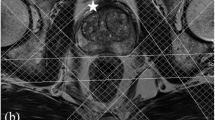

3D MRSI of a patient with histopathology confirmed prostate cancer. The patient was measured at 3 T with an endorectal coil for signal reception and a GOIA-sLASER sequence for VOI (voxel of interest) selection of the prostate. The yellow box indicates the field of view and the white box the VOI. The hatched bars represent the OVS slabs. For further MR measurement details see [28]. On the T2w MR image with the MRSI voxel grid, the location of a tumor voxel (A) and a benign voxel (B) are indicated with circles to better represent their actual shape which is spherical due to the point spread function. Representative MR spectra from tumor tissue and benign tissue are shown in panel A and B, respectively, illustrating decreased citrate and spermine and increased choline signals in the tumor lesion. Indicated are the signals for the prostate metabolites: citrate (Cit), choline (Cho), spermine (Spm), creatine (Cr), taurine (Tau) and myo-inositol (mI). Under the panels also histopathology slides are shown, illustrating the reduced luminal space in a cancer lesion in comparison with a healthy tissue (purple arrow)

It is common to apply outer volume saturation (OVS) bands, positioned around the prostate to reduce extraprostatic lipid signals (Fig.1). All spins in these bands are excited and then dephased by crusher gradients. OVS pulses were developed to compensate for poor edge profiles, B1 field inhomogeneity and chemical shift errors, such as very selective saturation (VSS) pulses with reduced B1 and T1 dependency [146]. The OVS slabs are usually placed manually, which is subjective and time-consuming, and limits the number of slabs to be placed. Therefore, automated algorithms have been developed, to optimize orientation, timing and flip angle setting of the VSS pulses following the shape of the prostate [147, 148]. Also, supervised 3D fully convolutional networks have been developed, for automatic prostate MRI segmentation [149], that can be extended to MRSI. As OVS selection may affect spectra of voxels at the edge of the prostate it is recommended to keep the number of slabs low and rely on the proper implementation of other options for lipid signal suppression (see above).

Metabolite signals in prostate MR spectra can be evaluated qualitatively, for instance, by visually inspecting signal intensity decreases of Cit and Spm and a signal increase of Cho as spectroscopic signatures to identify cancer lesions. However, as this is subjective it is preferred to employ quantitative methods, for instance by peak fitting, either in time or frequency domain. Most MR systems have software to determine peak areas, but it is also possible to export MRS data to specialized spectroscopic processing packages, such as LCModel [170, 181], jMRUI [182, 183] and Tarquin [184]. Because of the use of endorectal coils with an inhomogeneous receive B1 field by which signal intensity of the coil drops towards the ventral parts of the prostate, it has become custom to calculate signal ratios, avoiding intrinsic spatial variations in signal intensity. Because it is not always feasible to resolve Cho from Cr and Spm signals, in particular at 1.5T and with PRESS sequences, the most often used ratios are (Cho+Cr)/Cit and (Cho+Spm +Cr)/Cit [18]. With better resolution, e.g., at 3T, it is common to also use Cho/Cr [81] and Cho/Cit ratios. For the localization and characterization of cancer lesions, threshold values for these ratios are determined and ratio maps constructed (Fig. 4c). With phased array coils, which have a homogeneous B1 receive field within the prostate, it is possible to evaluate and map the signals of individual metabolites [81].

3D MRSI identifies correct tumor lesion after ambiguous T2 and DWI MRI in the mpMRI examination of a patient with serum PSA of 4.3 ng/ml. The MR investigations were performed at 3 T with a phased array coil for signal reception. For details see [111]. A Transversal T2 w MRI shows at least two locations with low signal intensity suspicious for cancer in the left and right side of the transition zone (TZ) of the prostate (white arrows). B Both these locations have high intensities in high b value maps suggesting the presence of tumor tissue. C This assignment seems to be confirmed by ADC maps with low intensities at both positions. D A metabolite ratio map obtained from 3D MRSI with a GOIA-sLASER sequence shows a hot spot for only the left TZ location. An MR spectrum obtained from this location shows a low citrate and increased choline signal compared to the right TZ location. This identifies the left TZ lesion as cancer tissue and the right TZ lesion as benign. This was confirmed by histopathology of biopsies from both locations, which identified the left TZ location as a low-risk cancer lesion and the right TZ location as benign. Cho choline; Cit citrate